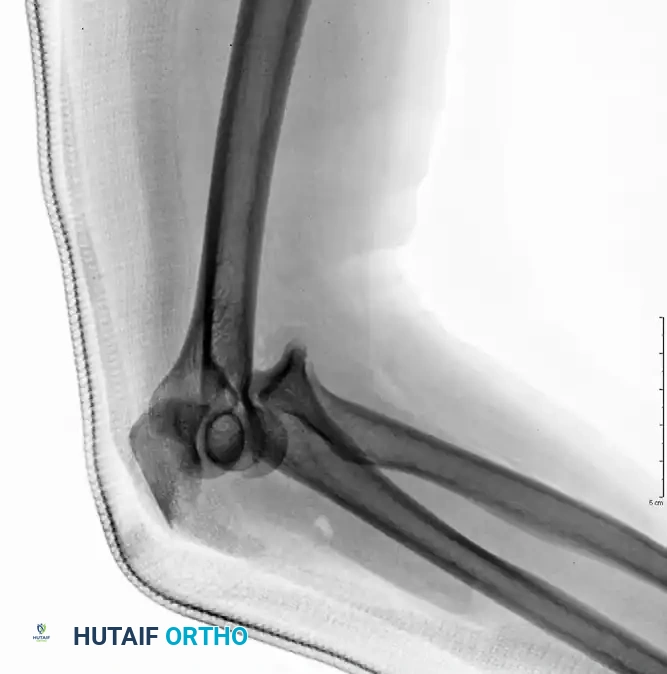

Preoperative Transolecranon Fracture-Dislocation:

Fixation with Lag Screws and Plate Spanning Entire Injury (AP View):

Fixation with Lag Screws and Plate Spanning Entire Injury (Lateral View):

Fixation with Lag Screws and Plate Spanning Entire Injury (Oblique View):

In an anterior transolecranon fracture-dislocation, the mechanism involves the distal humerus imploding through the olecranon. This results in an anterior ulnohumeral dislocation. Crucially, in a true transolecranon injury, the proximal radioulnar joint (PRUJ) remains anatomically preserved, and the collateral ligaments (MCL and LCL) are typically intact.

These injuries vary in complexity, often presenting with extensive comminution and coronoid involvement. The routine treatment protocol demands anatomical reconstruction of the greater sigmoid notch articular surface followed by rigid plate fixation. The coronoid must be reduced and stabilized with lag screws first, followed by provisional articular reduction, and finally, a robust plate spanning the entire zone of injury.